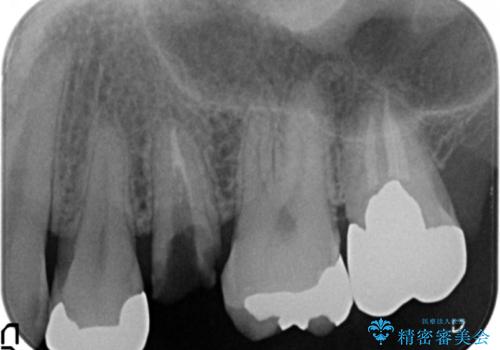

- 奥歯のかぶせ物が土台ごとはずれてしまったことを主訴に来院された患者様です。

残根状態になっている左上の小臼歯(左上5)を精査したところ、う蝕が歯肉縁下まで進行しており保存不可能な状態でした。

患者様のご希望により、抜歯後インプラント治療を行いました。